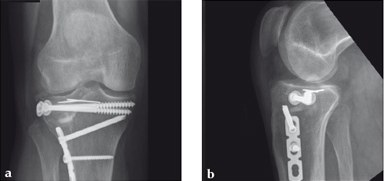

Case 2: A 38-year-old man sustained a lateral tibia plateau fracture (Müller AO Classification 41-B.3/Schatzker type II).

(Case provided by Michiel Verhofstad, Tilburg, The Netherlands)

After opening the lateral wedge, the osteochondral fragment was reduced and maintained with two K-wires. A gap beneath this fragment was left. Subsequently, a 3.2 mm hole was drilled in the lateral wedge using an inside-out technique. Then the lateral fragment was reduced. A 3-hole buttress plate, followed by two subchondral compression screws were used for final fracture fixation. Finally, Norian drillable was injected in the gap through the predrilled hole. Weight bearing was started after 6 weeks. At 6 months the fracture had healed anatomically and the patient was complaint-free.